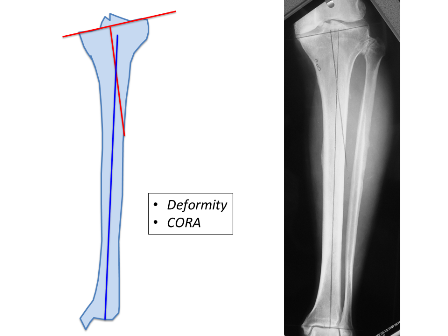

Indications for using a circular frame include leg length discrepancies requiring leg lengthening, non-unions, deformity corrections and bone infections, all of which come under the concept of limb reconstruction surgery. Deformity correction using the circular frame provides the flexibility of ensuring that the limb is perfectly aligned (Figure 1A, 1B, 2A and 2B) to the mechanical axis along with leg lengthening, if required.

In this article, the technique of applying the hexapod circular frame for deformity correction in the tibia is discussed (Figures 4A to 4E). Introduction of the hexapod in the late 1990s, allowed deformity correction simultaneously in all 3 axes which has made deformity correction surgery extremely simple.